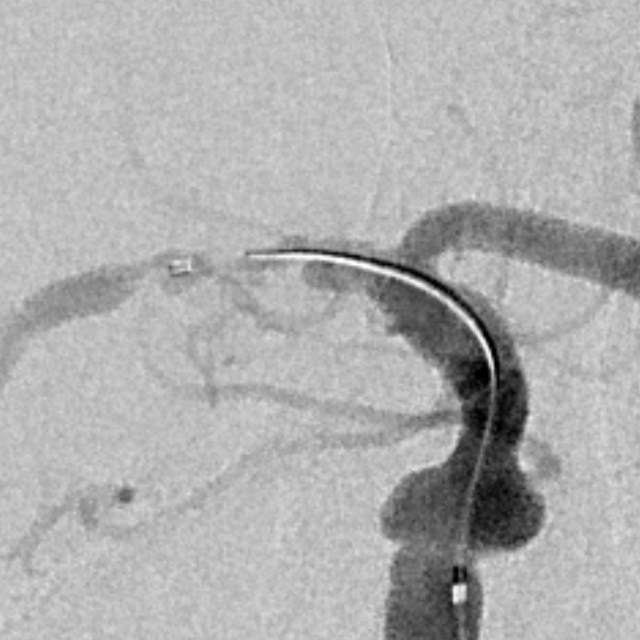

78岁老年男性,最近一个半月来已经和家里人没法正常交流,认知能力大幅下降,在农村,可能也就认为年龄大了,听天由命了。可老人家就是福大命大,有亲戚做医生,间隔17天先后为老人做了两次头颅MRI,发现脑梗塞,右侧血管长节段严重狭窄,右侧大脑半球缺血严重(图6,满江红),手术风险大……,家属经过反复咨询、犹豫、权衡,选择了保守治疗,毕竟老人年龄大了,手腿现在还能动,手术也有风险,时机也不是太好,国外研究不推荐,国内研究也不支持,保守治疗似乎是个不错的选择。然而,保守期间,患者反复出现脑梗塞,认知能力进行性下降,最终促使家属决定采用外科干预。然而,对医生而言,在梗塞的急性期处理这种长节段密布分支血管的病变风险不言而喻,而一味的观望和等候肯定不是最佳选择。过一点,可能出血;欠一点,可能闭塞。全面认真评估后,我们顺利为老人家完成了I期治疗,老人家的“火焰山”(图6)变成了“绿油油”充满生机的田野(图14),缺血明显改善,认知能力大幅提高,术后就能和家人正常交流了,也记起了很多以前忘记的事情……,家人很开心。